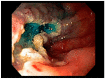

Gastric and esophageal tumors are diverse neoplasms that involve mucosal and submucosal tissue layers and include squamous cell carcinomas, adenocarcinomas, spindle cell neoplasms, neuroendocrine tumors, marginal B cell lymphomas, along with less common tumors. The worldwide burden of esophageal and gastric malignancies is significant, with esophageal and gastric cancer representing the ninth and fifth most common cancers, respectively. The approach to diagnosis and staging of these lesions is multimodal and includes a combination of gastrointestinal endoscopy, endoscopic ultrasound, and cross-sectional imaging. Likewise, therapy is multidisciplinary and combines therapeutic endoscopy, surgery, radiotherapy, and systemic chemotherapeutic tools. Future directions for diagnosis of esophageal and gastric malignancies are evolving rapidly and will involve advances in endoscopic and endosonographic techniques including tethered capsules, optical coherence tomography, along with targeted cytologic and serological analyses.